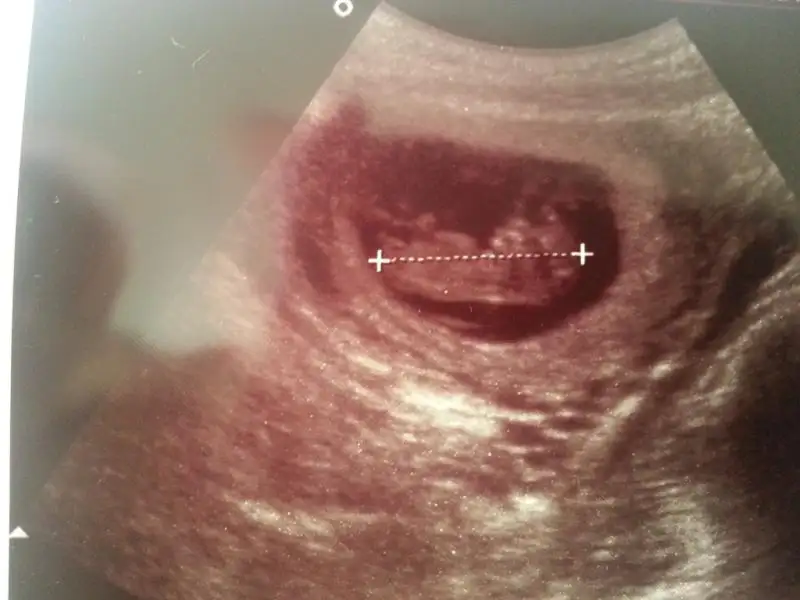

ana senin bebek benimkine göre ters duruyor kafası diğer tarafta maşallah büyümüş ne güzel.